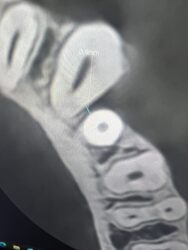

I have this implant case for tooth #28. I am worried about the anterior loop of the IAN here. It looks like it terminates at slice 62 and 63 but then I have a circular radiolucent area in slice 65. Do you think this is still the mental? If so I have about 10mm from the crest of the ridge. Do you think I’d be safe with an 8 mm implant here?

Just looking at what you provided it looks like there is sufficient room for an 8mm implant and that other slice I believe around 65 just looks like a void around the bone that looks similar to the pano version of the cbct and doesn’t present in other slices, nerve appears to be below that area.